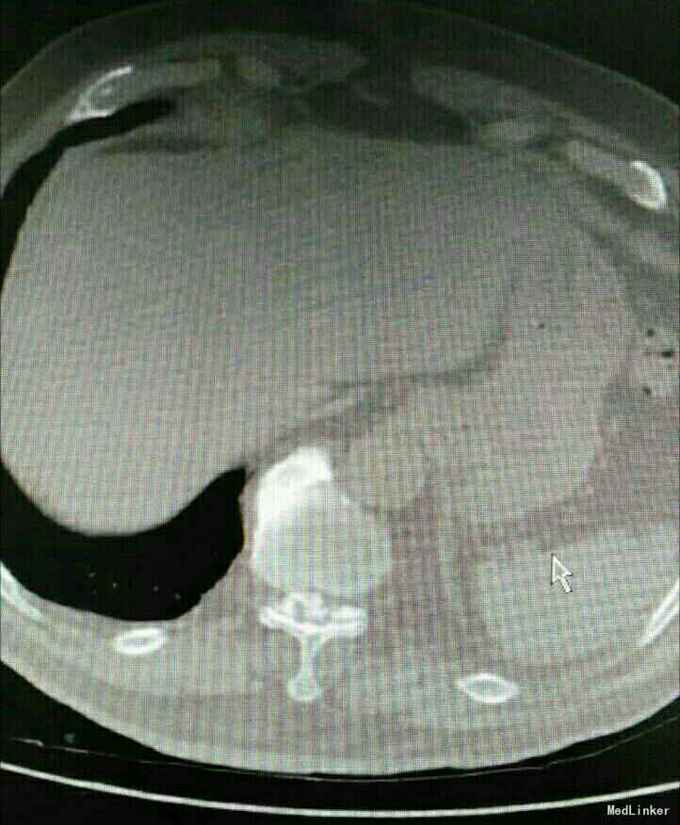

又是严重的胸椎黄韧带骨化,胸10-11、胸11-12。

渐进性双下肢感觉运动障碍10月,大小便障碍10天。